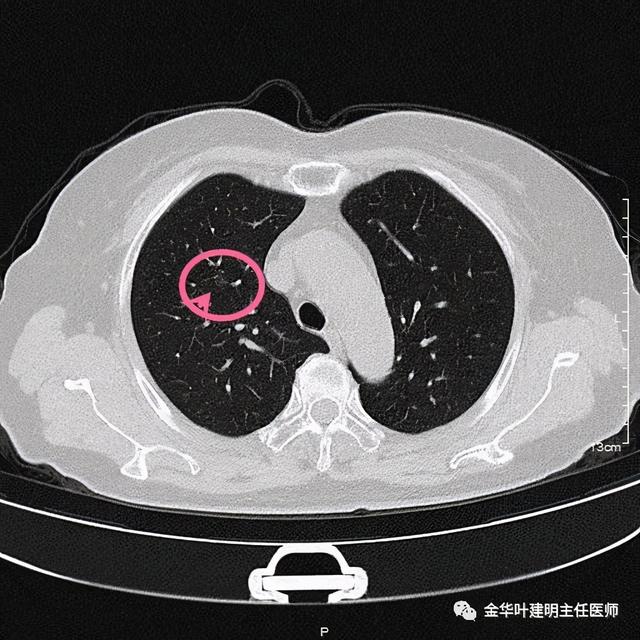

在右上叶前段(估计与尖段相邻近)有一直径约8毫米的淡磨玻璃结节 , 中间有一小点状偏高密度 , 从影像上看 , 考虑不典型增生或原位腺癌可能性大 。 再反过头再去找平扫的图像 , 真的不容易发现呀:

文章插图

这么淡的磨玻璃!